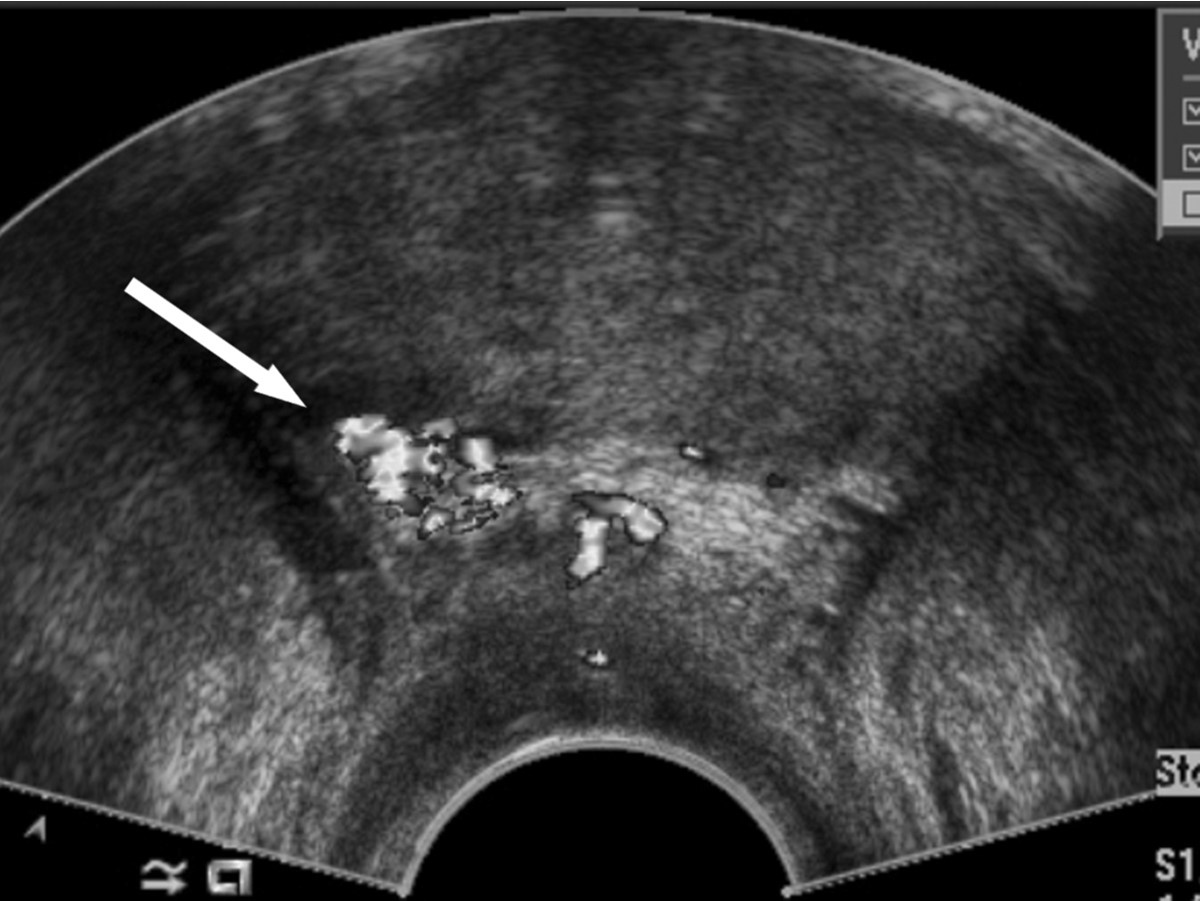

내원하여 시행한 CT, MRI 검사 상 전립선 내 특이 소견 없었고, 경직장 전립선 초음파 검사(TRUS) 상 전립선 내에는 특이 소견 없었으나 전립선 주변부, 우측 뒤쪽 부위에 약 lcm 크기의 혈류의 유입(빨강색)/유출(파란색) 신호가 뒤섞인 채 증가되어 있는 국소 병변이 관찰되었다 (Fig. 1A).

A. Transrectal ultrasonography shows about 1cm sized focal area with increased Doppler signal in the right posterior periprostatic region. Doppler signals are intermixed with the inflow of blood (signified by red) and the outflow of blood (pictured in blue).